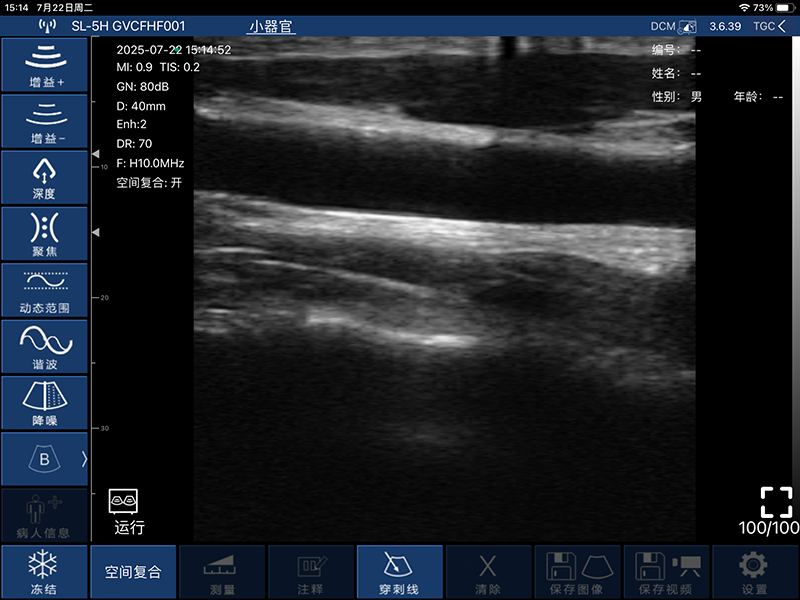

带指套探头的掌上彩超,小小的掌超主机放在口袋可随处走,手指套着探头即可完成打图成像,让手不再需要握着探头而可解放出来还能拿其他东西,特别适合术中等应用

- 扫描方式:电子阵列扫描

- 扫描宽度:40mm

- 扫描深度:20-100mm,可调

- B模式